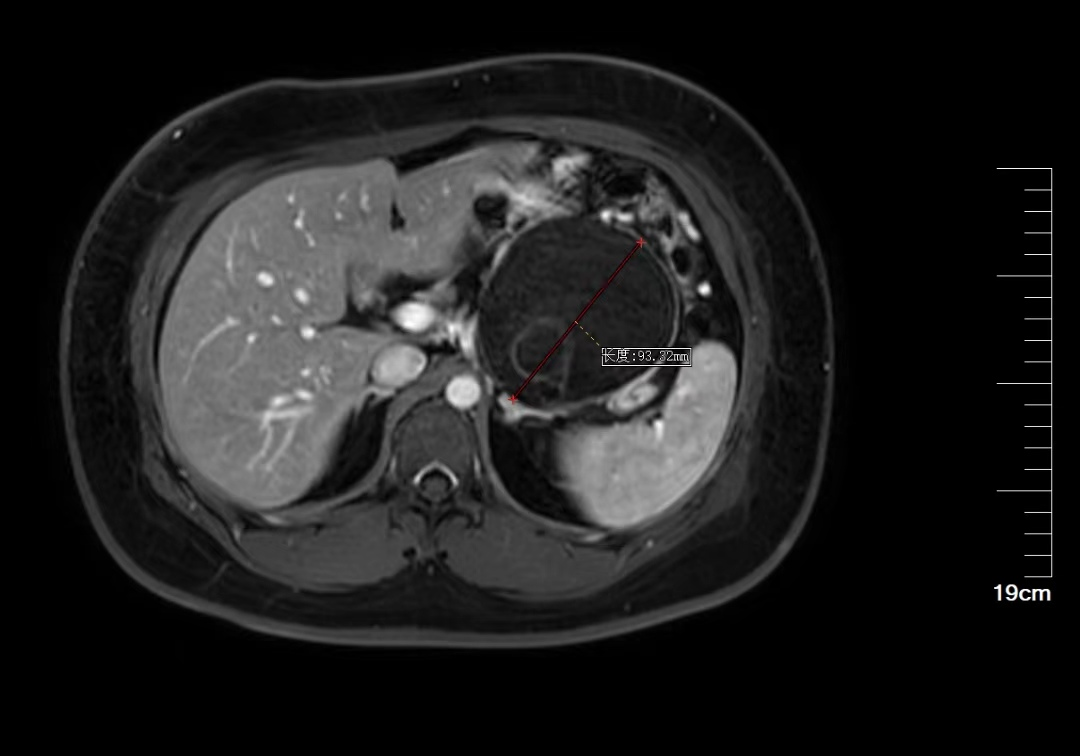

25岁的吕女士,2024年5月行常规体检时查上腹部CT平扫见胰体尾部一巨大类圆形囊性密度灶,大小约94*92mm,考虑胰体尾部囊性占位。鉴于患者年龄仅25岁,未婚,患者及家属强烈要求行微创手术治疗。经多方咨询,至我院肝胆胰外科门诊就诊。古主任在阅看患者外院影像片后,考虑患者胰体尾巨大囊性占位,与脾动静脉分界不清,需术中进一步探查明确脾脏是否需同时切除。

胰体尾巨大囊性占位MRI